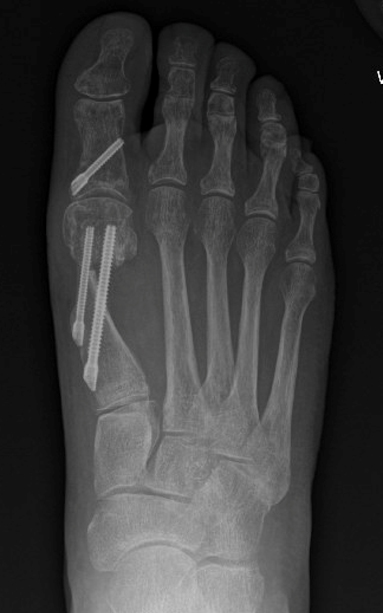

TOTAL ANKLE REPLACEMENT :: ORIF CALCANEUS :: ORIF ANKLE FRACTURE DISLOCATION :: COMPLEX BUNION AND LESSER TOE CORRECTION :: TALUS FRACTURE -1 :: TALUS FRACTURE -2 :: LISFRANC REPAIR :: COMPLEX TRIPLE ARTHRODESIS 1 :: COMPLEX TRIPLE ARTHRODESIS 2 :: MINIMALLY INVASIVE BUNION REPAIR 1 :: MINIMALLY INVASIVE BUNION REPAIR 2 :: ARTHROSCOPIC CARTILAGE REPAIR :: TENEX SPUR DEBRIDEMENT :: Haglunds Debridement and Achilles Repair